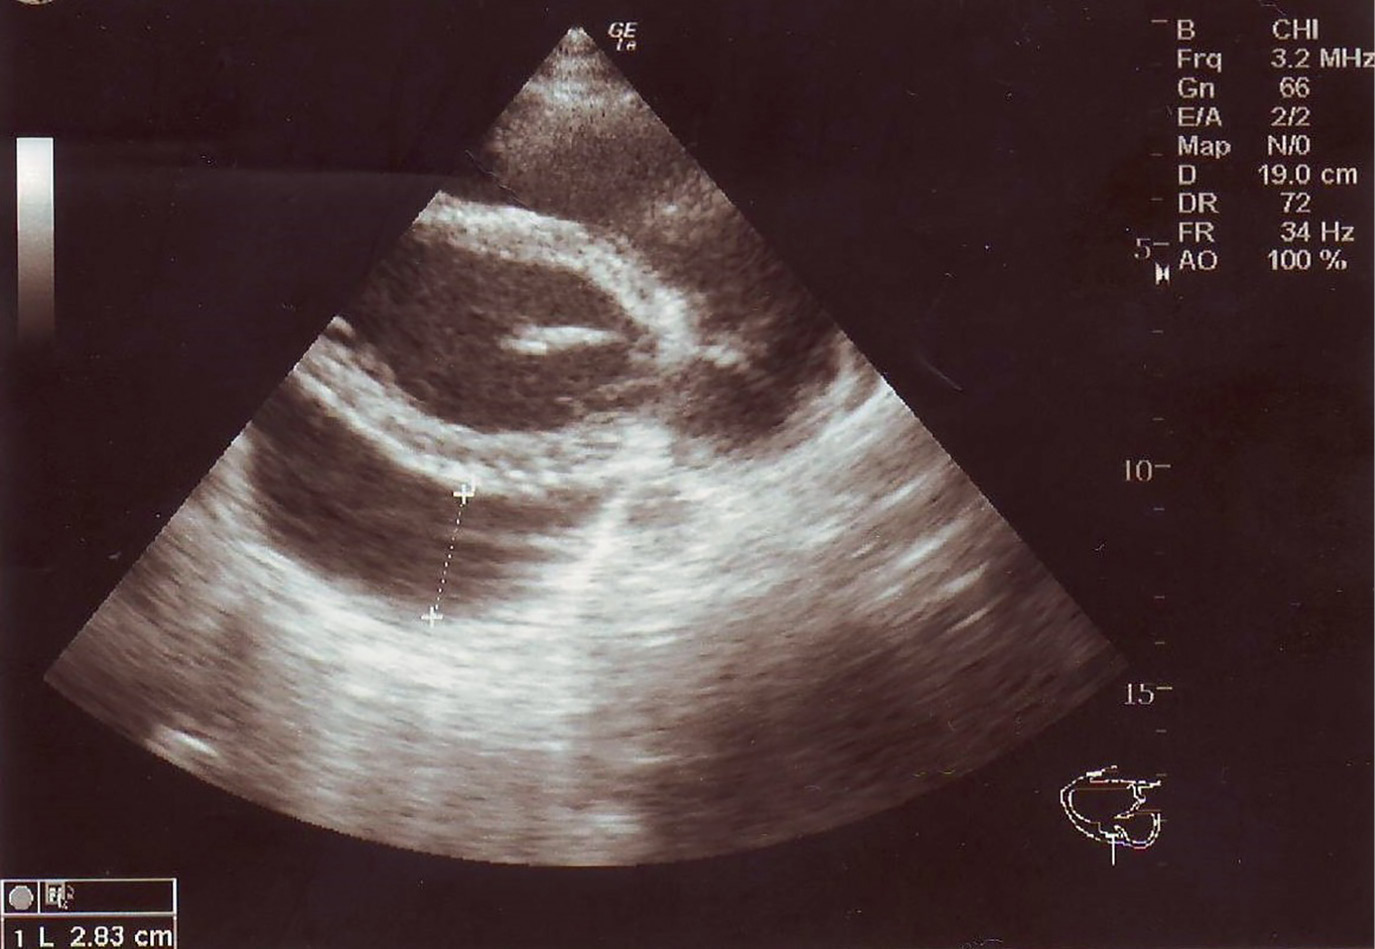

2. Рисунок 2. УЗИ сердца. Гидроперикард в области верхушки. | |

Тема | ||

Тип | Исследовательские инструменты | |

Посмотреть

(186KB)

|

Метаданные ▾ |